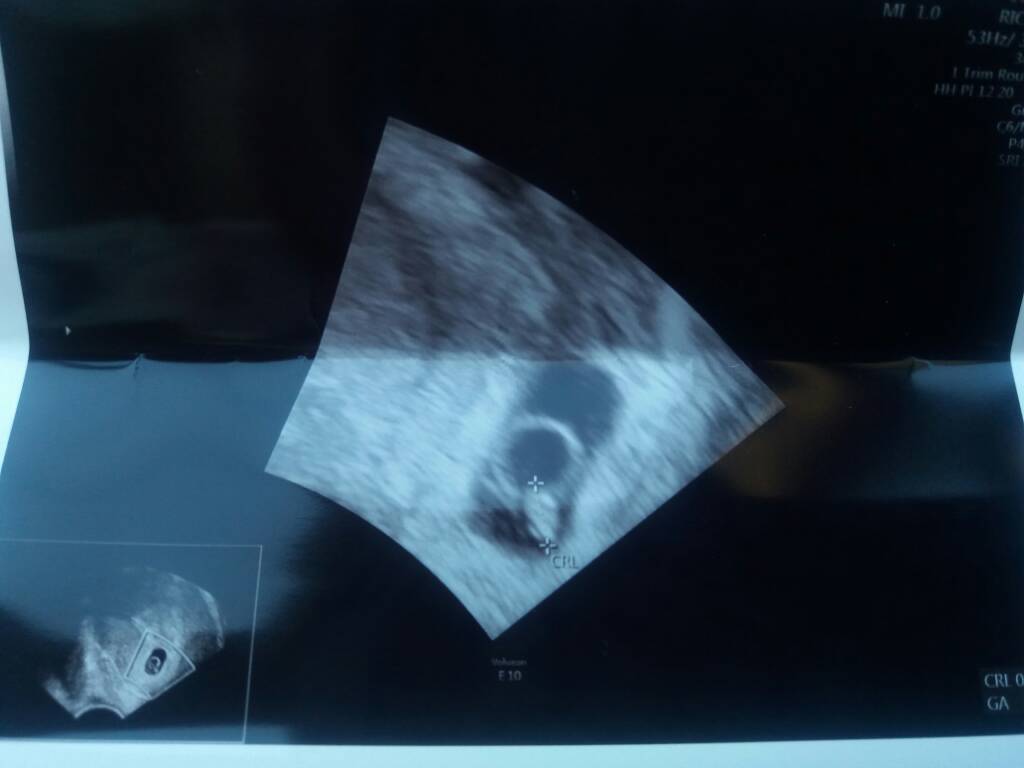

Mamy całe 3.5mm człowieka z bijącym idealnie serduszkiem 109 i wysoko umiejscowiony wszystko dobrze co do dnia [emoji7]♡ Słuchaliśmy coś pięknego... [emoji4]

Zobacz załącznik 848761